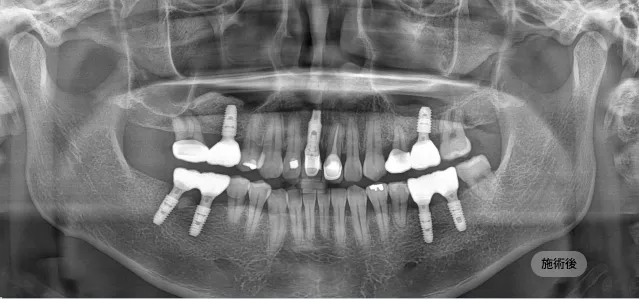

画面をドラッグして前/後を比較してみてください

計画された位置に人工歯根(インプラント体)を正確に埋入します。必要に応じて、不足している骨を補う骨造成(骨移植)を同時に行います。

歯肉の形態を整え、アバットメント(支台)を接続した後、周囲の歯と調和する最終補綴物(頭部)を製作し、装着します。

長く、健康に使えるインプラントのために ブランシュ歯科は施術より「設計」を先に考えます。

精密CT、3Dシミュレーションで 正確な骨の状態を分析します。

精密診断